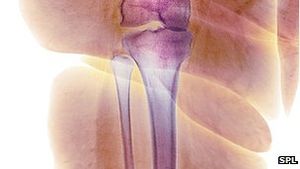

Osteoporose: Forscher weisen Fettsucht als neuen Risikofaktor nach (SPL)